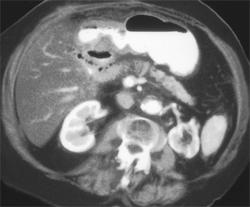

Gastric Varices